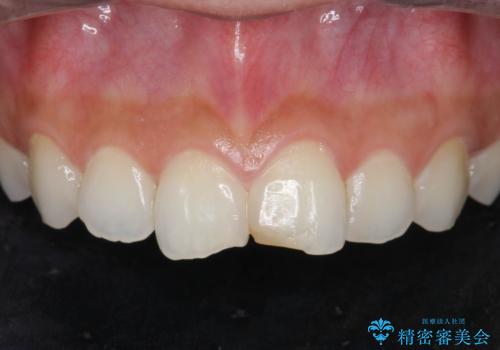

すり減った前歯の形態回復

担当医 大元洋佑